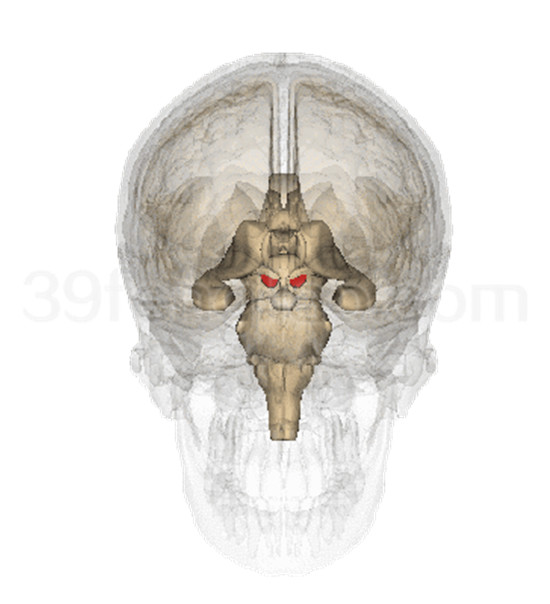

中枢部分包括脑和脊髓,分别位于颅腔和椎管内,两者在结构和功能上紧密联系,组成中枢神经系统。

脑部